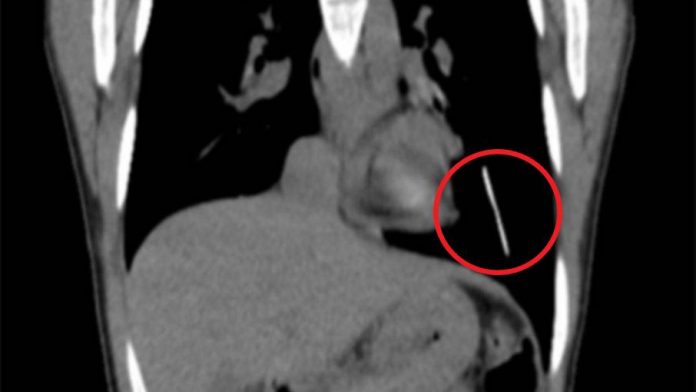

the 31-year-old patient, the Doctors finally found: the rods containing barium sulfate, it was seen on x-ray images of the chest area. A further CT scan confirmed that the plastic rod in a blood vessel of the left lower lung was stuck.

Lost bet, This x-ray image makes you speechless: man gets a year-long spoon in the neck